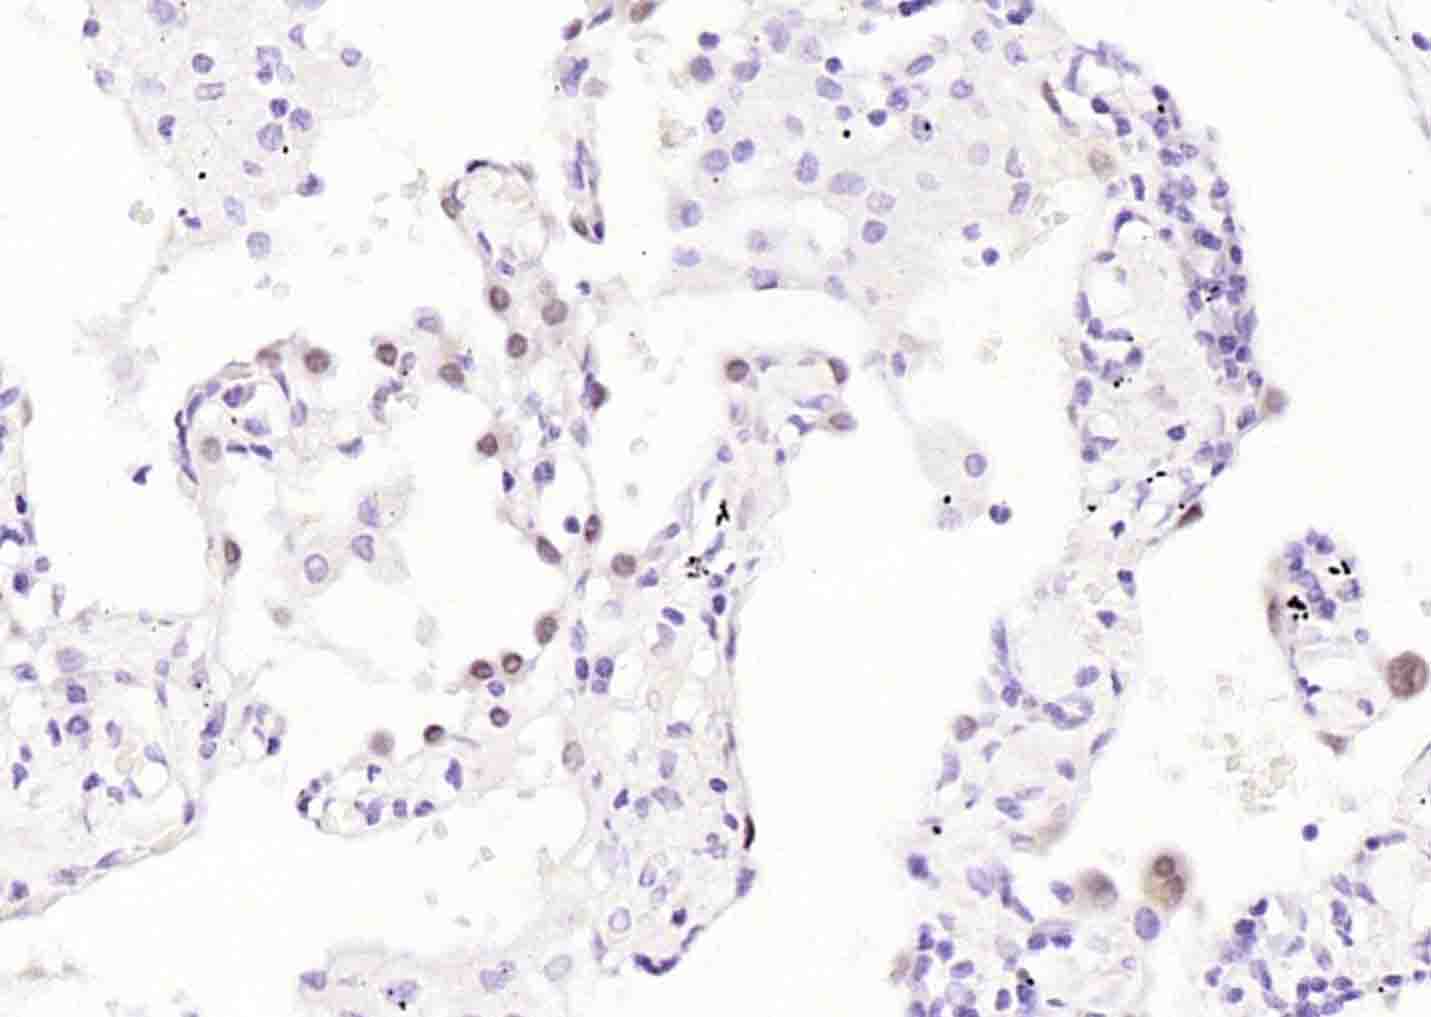

Paraformaldehyde-fixed, paraffin embedded (mouse lung ); Antigen retrieval by boiling in sodium citrate buffer (pH6.0) for 15min; Block endogenous peroxidase by 3% hydrogen peroxide for 20 minutes; Blocking buffer (normal goat serum) at 37°C for 30min; Incubation with (TTF1/NKX2-1 ) Monoclonal Antibody, Unconjugated (bsm-34158M) at 1:200 overnight at 4°C, followed by operating according to SP Kit(Mouse)(sp-0024) instructionsand DAB staining.